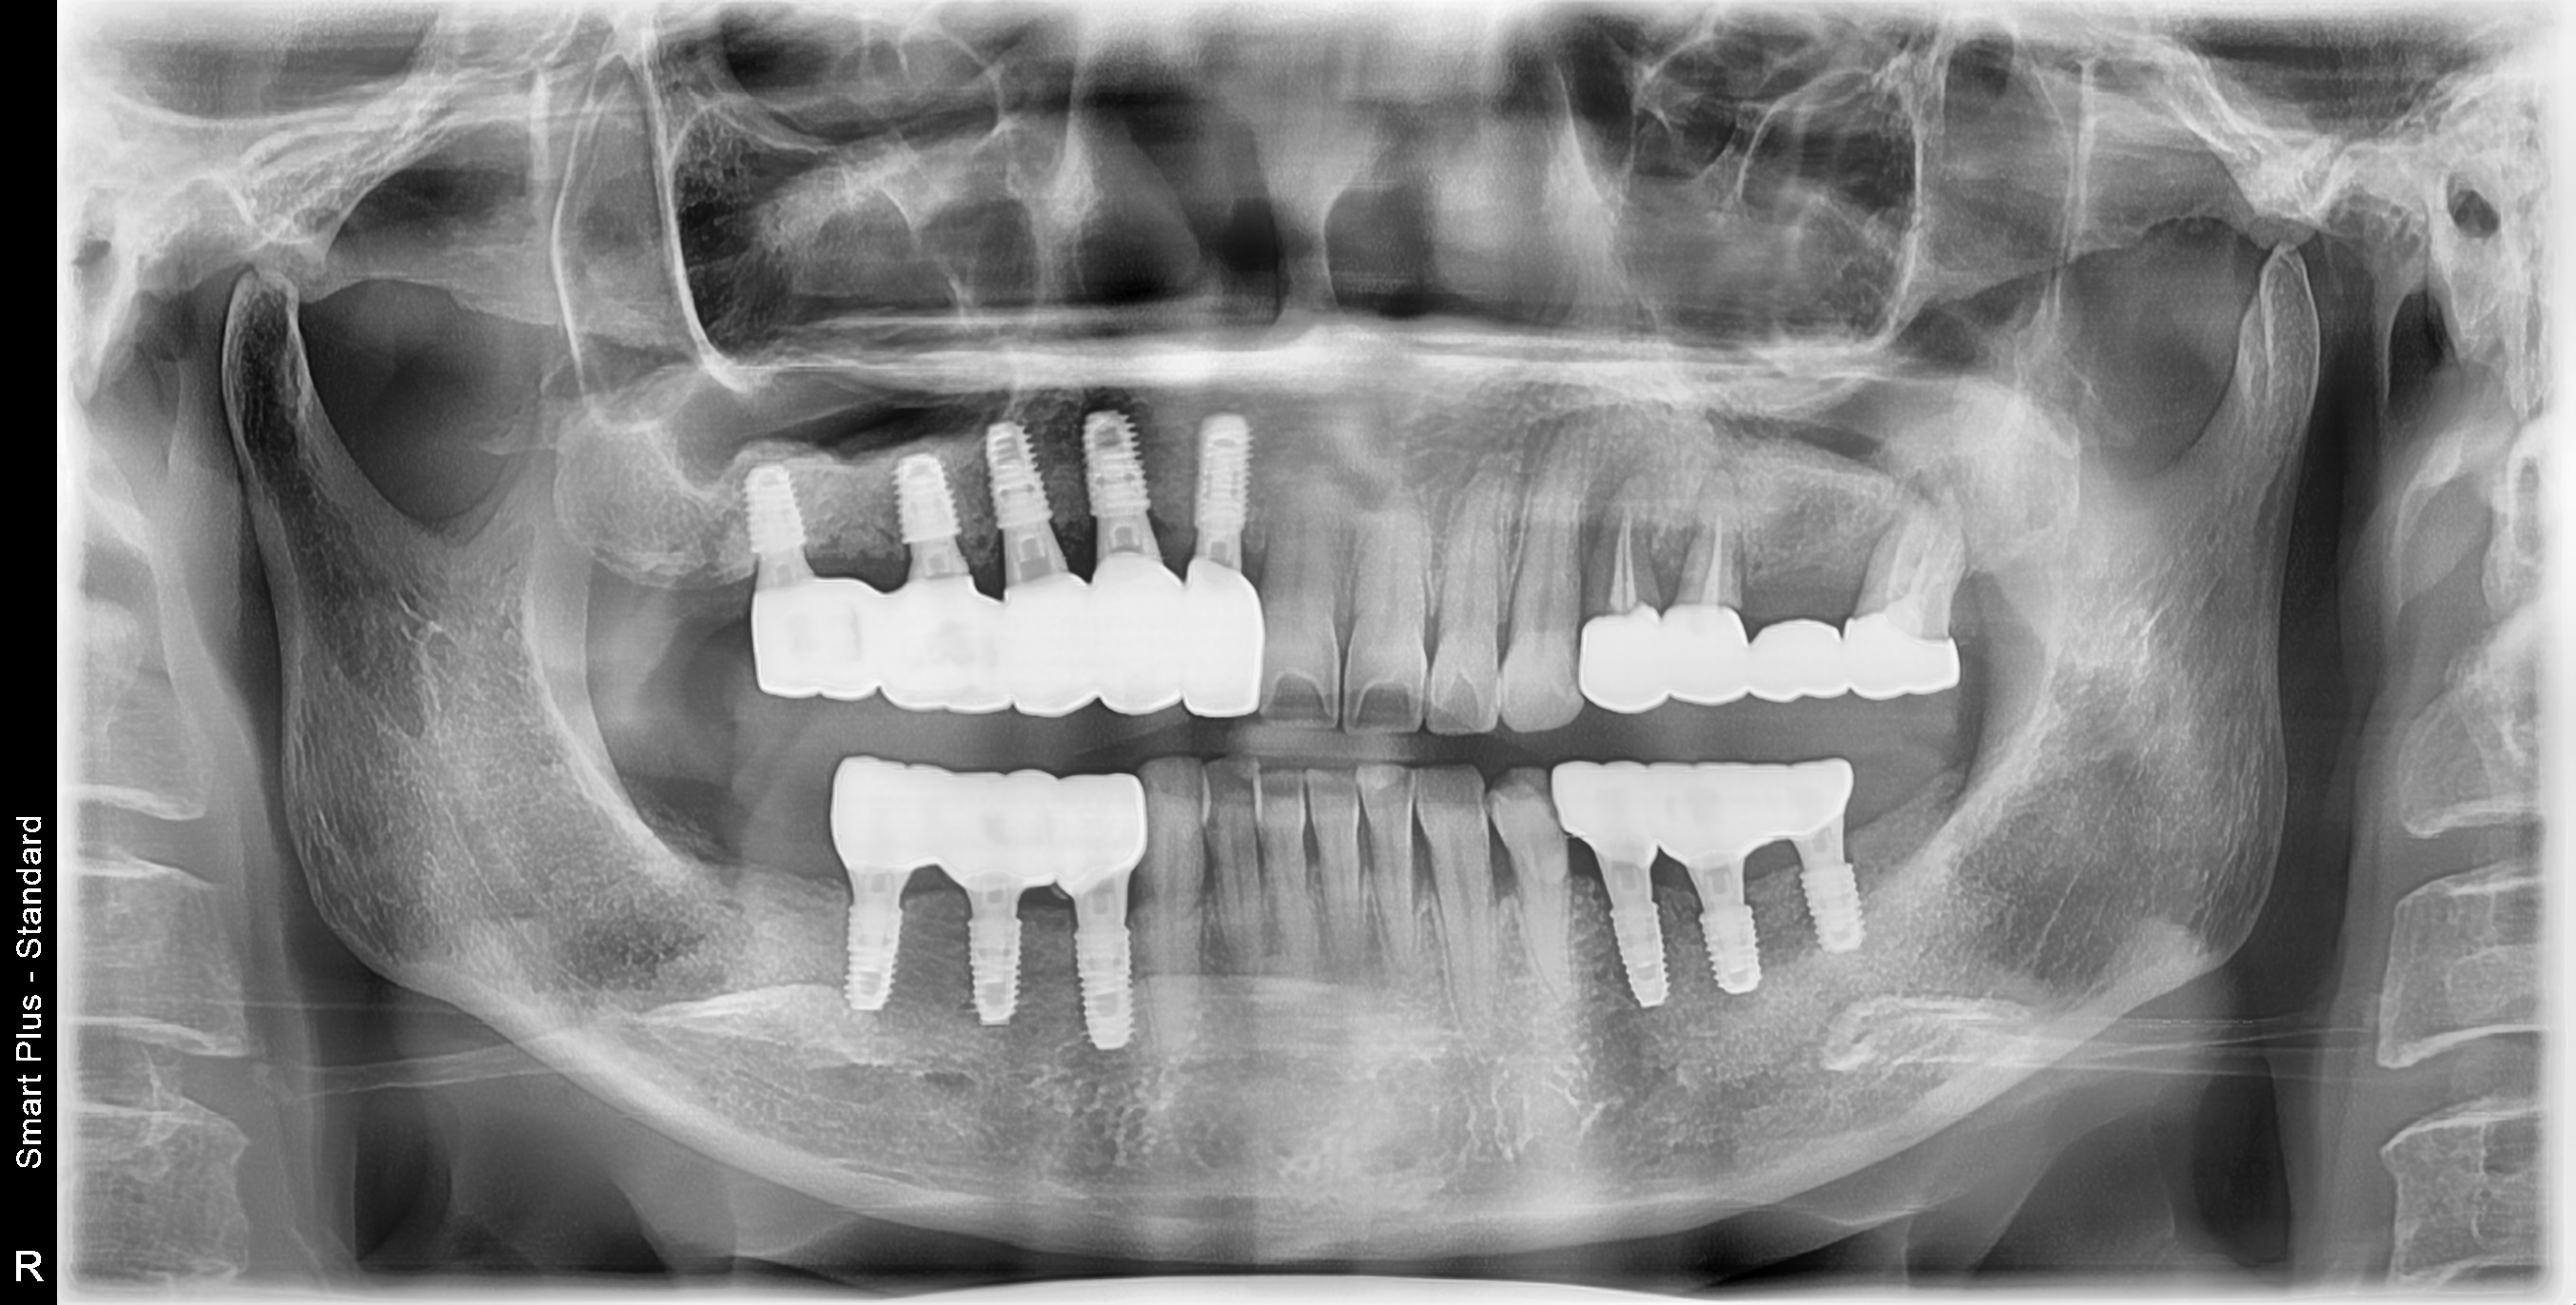

[임플란트] 제목 : 임플란트에 의한 교합기능 재건

임플란트에 의한 교합기능 재건